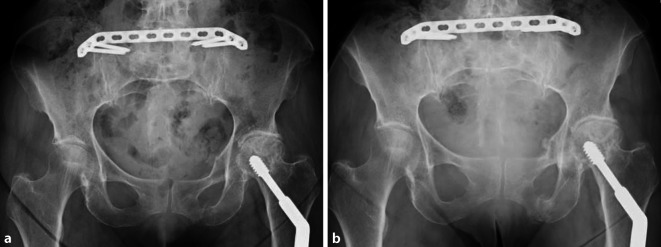

Wir stellen den Fall einer 86-jährigen Patientin vor, die am 24.12.2020 in ihrer Wohnung gestürzt war und aufgrund von zunehmenden immobilisierenden Schmerzen am 27.12.2020 stationär aufgenommen wurde. In der bei der Aufnahme durchgeführten Beckenübersicht zeigte sich eine acetabulumnahe vordere Beckenringfraktur links. In der CT wurde darüber hinaus auch eine Beteiligung des hinteren Beckenringes festgestellt. Die Frakturen wurden nach Rommens und Hofmann in FFP IVb klassifiziert. Wesentliche Vorerkrankungen bestanden nicht. Im Aufnahmelabor zeigte sich an pathologischen Werten ein leicht erhöhtes CRP mit 26,5 mg/dl (in der präoperativen Kontrolle rückläufig auf 2,7 mg/dl) bei ansonsten normalen Laborbefunden. Klinisch klagte die Patientin über Schmerzen in der linken Leiste und über dem Sakrum. Auch unter suffizienter Schmerztherapie ließ sich die Patientin lediglich mit dem Rollator für wenige Schritte mobilisieren. Da sich unter konservativer Therapie auch am 5. Tag keine Besserung einstellte, willigte die Patientin in das ihr vorgeschlagene operative Verfahren ein. Vor der Verletzung hat sich die Patientin noch allein zu Hause versorgt und war gut mobil. Die operative Versorgung erfolgte mittels minimal-invasiver, winkelstabiler, dorsaler Beckenplatte (MIPLCP). Dieses Verfahren kommt bei uns primär zur Versorgung von Fragility fractures des Beckens zum Einsatz. Als Kontraindikation sehen wir eine Bettlägerigkeit an, die bereits vor der Verletzung bestand, sowie Weichteilprobleme (Dekubitalgeschwüre) oder vorliegende Infekte. Als Alternativverfahren kommt in unserer Klinik die iliosakrale Schraubenosteosynthese zur Anwendung. Durch die Versorgung mittels MIPLCP wird eine hohe Primärstabilität erreicht, und die Patienten sind postoperativ sofort unter Vollbelastung mobilisierbar. Insbesondere bei dem betagten Patientenkollektiv halten wir es für essenziell, die Immobilitätsphase so gering wie möglich zu halten. Die Patientin konnte ab dem ersten postoperativen Tag mit Vollbelastung mobilisiert werden. Die Wunden heilten primär. Zur weiteren Rehabilitation wurde sie am 10. postoperativen Tag in die Anschlussheilbehandlung entlassen. Bei der routinemäßigen Wiedervorstellung nach 8 Wochen war sie bereits im Wesentlichen ohne Hilfsmittel mobil und nahezu schmerzfrei. Analgetika wurden nicht mehr benötigt. Die Schrittgeschwindigkeit auf 4 m („gait speed“) betrug 5,6 s. Die im weiteren Verlauf durchgeführte konventionelle Beckenübersicht zeigte eine weiterhin regelrechte Implantatlage bei zunehmender Kallusbildung. Die CT-Abschlusskontrolle nach 6 Monaten steht noch aus.

Nach der abschließenden Röntgenkontrolle erfolgt der Wundverschluss. Um den Behandlungserfolg sicherzustellen, ist ein adäquater Verschluss der Weichteile von essenzieller Bedeutung. Nach Überprüfung der Bluttrockenheit (Vermeidung postoperativer Hämatome) werden die gesicherte Faszie des M. glutaeus maximus und die thorakolumbale Faszie fest über der Platte verschlossen (11:15). Danach erfolgt der weitere schichtweise Wundverschluss. Ein Rahmenverband, der die Wundflächen vor Druckbelastungen schützen soll, wird abschließend angelegt (13:20) (Abb. 3). Die Patienten werden sofort postoperativ mit physiotherapeutischer Hilfe und entsprechender Analgetikatherapie mit schmerzadaptierter Vollbelastung mobilisiert.

Postoperative Behandlung

Sofortige Vollbelastung möglich. Anlage eines „Rahmenverbands“ zum Schutz der Wunde vor vermehrtem Druck. Des Weiteren werden die Patienten angehalten, längeres Liegen auf dem Rücken zu vermeiden. Die Entlassung kann üblicherweise ab dem 10. bis 12. postoperativen Tag und dann entweder in die Anschlussheilbehandlung oder nach Hause erfolgen. Nahtmaterialentfernung nach 12 bis 14 Tagen. Röntgenverlaufskontrolle vor Entlassung und nach 6 bis 8 Wochen. Wenn möglich, CT-Kontrolle nach 6 Monaten (Abb. 4).